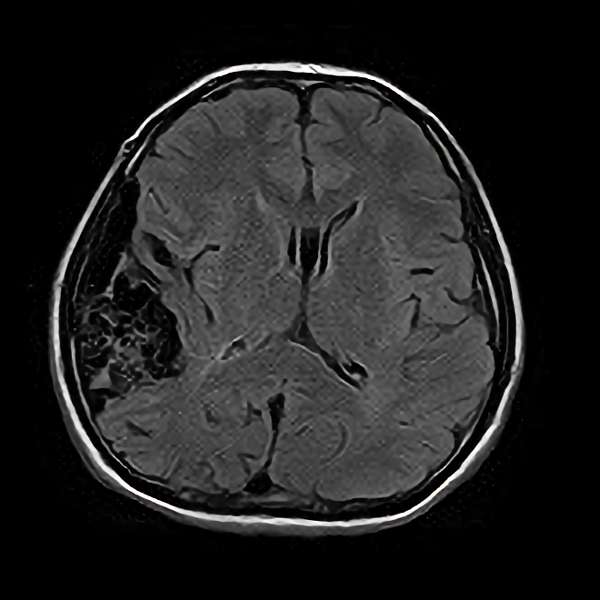

脳血管撮影

手術前

手術後